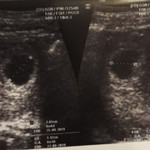

สอบถามคลายข้องใจผู้มีประสบการณ์คะ คือประจำเดือนมาล่าสุดวันที่ 27ธันวาคม61 ปัจจุบันประจำเดือนยังไม่มาตรวจเจอขึ้น2ขีด แล้วที่ผ่านมาวันเสาร์ที่2กุมภา62 มีเลือดออกสีน้ำตาลออกชมพูเท่าเหรียญ10ติดกกน. แล้วหายไป ไปหาหมออุลตร้าซาวไม่เจอเด็กหมอว่ามีความผิดปกตินะถ้าถุงขนาดใหญ่ต้องเจอเด็กหมอบอกทำใจจิตตกรอ1สัปดาห์หมอจะให้ยุติการตั้งครรภ์ สอบถามผู้รู้เพื่อกำลังใจ หมอไม่แน่ใจอายุครรภ์ กลัวน้องไม่อยู่คะ เคยแท้งเมื่อปีที่แล้ว อยากได้ลูกมากคะ